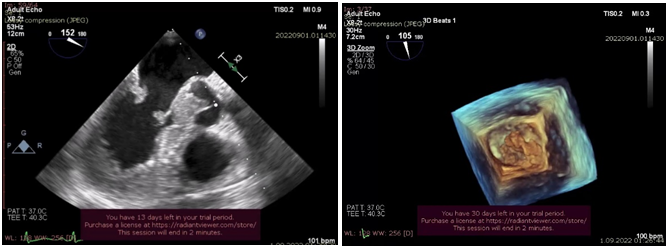

NBTE şübhəsi olan xəstələrin qiymətləndirilməsi üçün seçilən ilk görüntüləmə üsulu TTE-dir. Bu qeyri-invaziv metodun üstünlükləri - geniş əlçatanlığı, yüksək temporal rezolyusiya və hemodinamik nəticələri, xüsusən də qapaq disfunksiyalarını təyin etmək qabiliyyəti aiddir. İE üçün əsas exokardioqrafik meyarlar - vegetasiya, perianulyar abses, psevdoanevrizma, perforasiya, fistula, qapaq anevrizması və protez qapağın dehissensidir. Exokardioqrafiya vegetasiyaların sayını, ölçüsünü, formasını, yerini, exogenliyini və hərəkətliliyini qiymətləndirir, buna görə də emboliya riskini proqnozlaşdırmaq üçün önəmlidir.